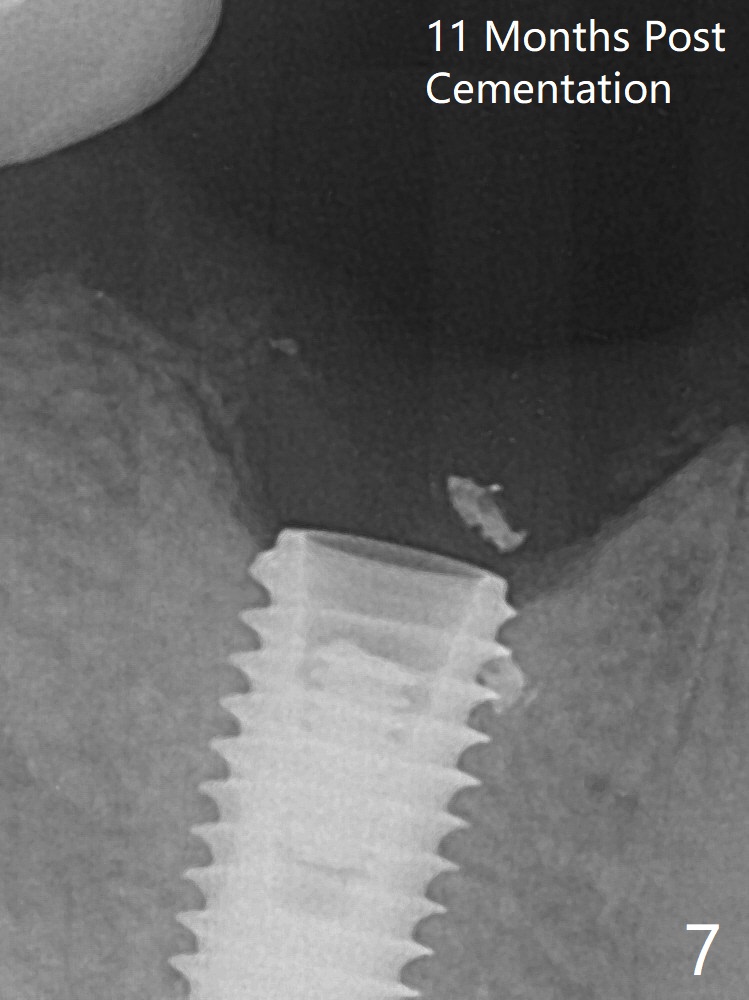

When the residual roots of the tooth #30 (Fig.1) are removed, the buccal crest is found ~ 2 mm apical to the lingual one (Fig.2 <); while the initial depth of osteotomy is 11.5 mm (yellow lines), the parallel pin is 10 mm long. To place a 5x11.5 mm implant at the level of the buccal crest (Fig.4 (>45 Ncm)), subsequent osteotomy depth is 13 mm using the lingual crest as a landmark (Fig.3 (4 mm drill in place)). After insertion of a 5.7x5.5(3) mm abutment, Vanilla Graft is placed (Fig.5 * with 2 mm buccal gap). The abutment with a provisional is loose 4 months postop (Fig.6). The permanent restoration is cemented 6 months postop. The abutment screw is loose and fractured 8 and 11 months post cementation, respectively (Fig.7). The fractured screw seems to be loose within the implant well and is easily re-winded out using Screw Removal Kit (sr-kit.html). When the crown/abutment at #30 is loose 2nd time 1 year 7 months post cementation (Fig.8 taken post retightening), the screw at #19 fractures. The tooth #2 needs a crown. The patient cannot use the anterior teeth, since the teeth #8 and 9 have root fracture. Can extraction and bone graft increase bone height? The screw re-fractures 9 months later (Fig.9). The dislodged crown is sectioned; the abutment is reseated completely (Fig.10) for a new crown. The tooth #2 needs RCT, B-U and crown, while the tooth #1 extraction (Fig.11).